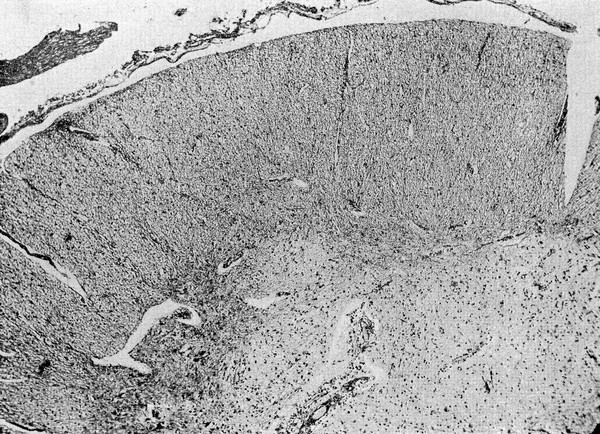

A practical treatise on tropical dysentery, more particularly as it occurs in the East Indies ; illustrated by cases and appearances on dissection : to which are added, practical treatises on scorbutic dysentery, on the morbus chylopoieticus and gastrodynia a fame ; with some facts and observations relative to scurvy in general, and a short account of the scorbutic disease that appeared at the Penitentiary, Millbank, Westminster / By R.W. Bampfield, Esq. Surgeon.

Bampfield, R. W. (Robert William), -1827.Date: 1823